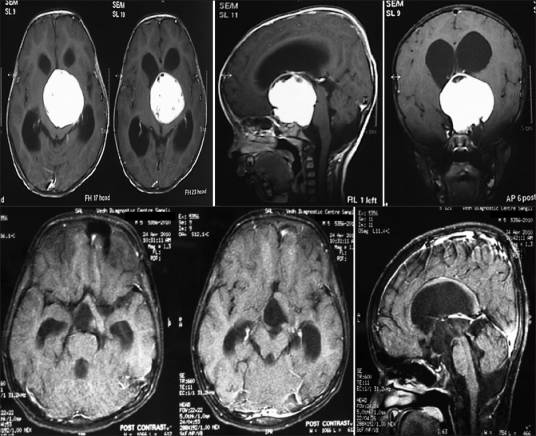

(一)CT、MRI检查:

垂体癌及其他恶性肿瘤的CT与MRI影像表现不具特征性。病程短,发展快。瘤体一般较大,形态多不规则,瘤体内密度不均,常有液化坏死区所呈现的低密度或长T1信号,长T2信号等影像表现。向鞍上及鞍旁发展,易造成周围结构的明显侵犯和破坏,尤其海绵窦有侵犯或有邻近神经组织侵犯者应高度怀疑其为恶性。一般难以与侵袭性垂体腺瘤相鉴别。